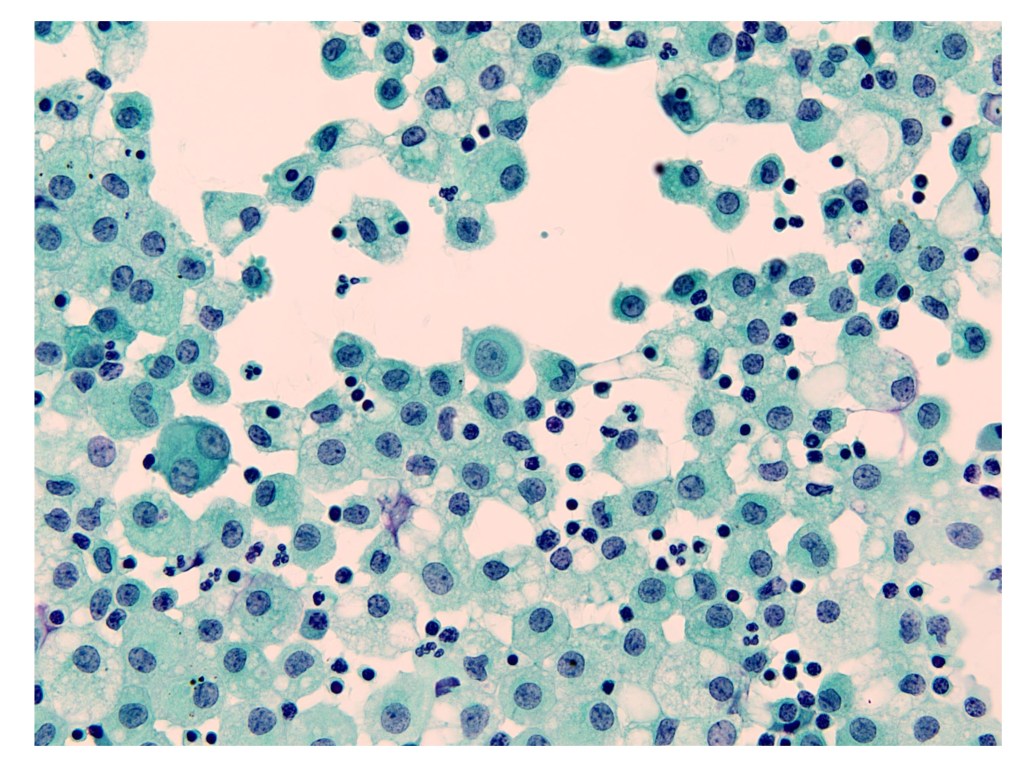

Course 4. Small Round Cell Pattern in Liquid-based Cytology